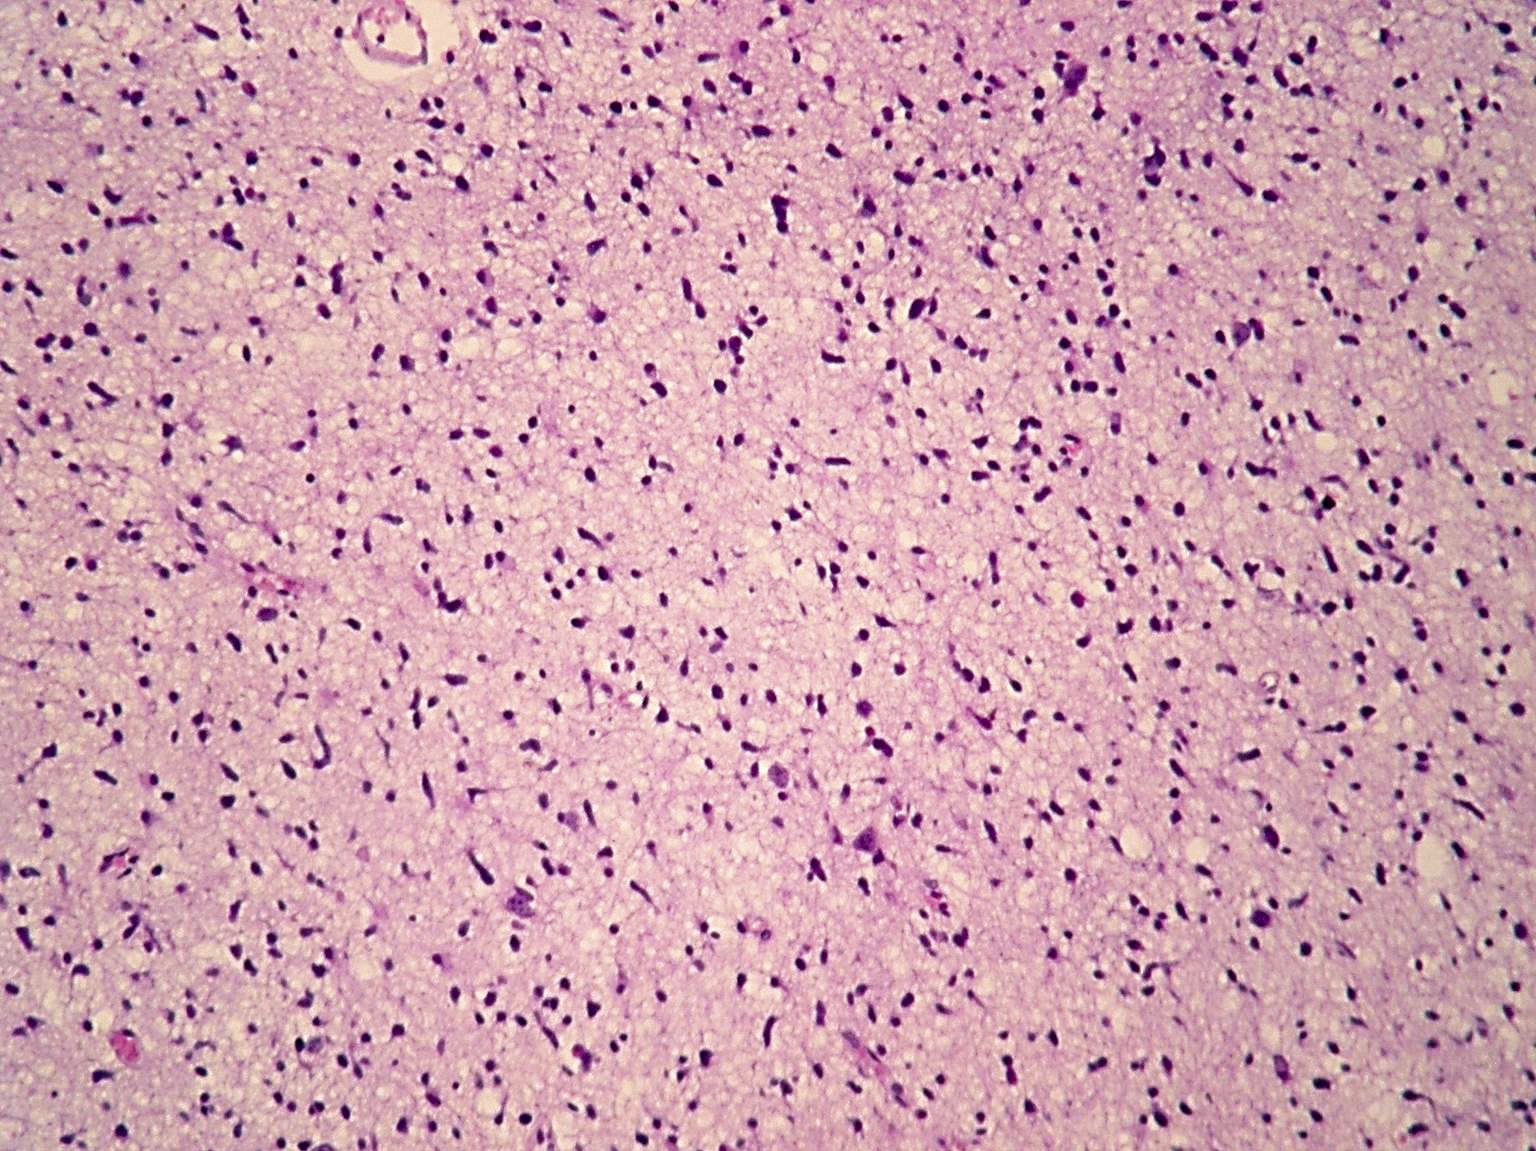

Microscopic (histologic) description

- Diffusely infiltrating tumor cells with oval to elongated astrocytic nuclei and varying appearance of tumor cytoplasm and fibrillar glial processes (Acta Neuropathol 2015;129:789)

- At the periphery, tumor cells may infiltrate in a diffuse single cell pattern, often with entrapped neurons and axons

- Cellular morphology is variable, even within a single tumor

- Commonly there is a mix of cells with elongated nuclei and fine fibrillar processes, cells with eccentric nuclei and glassy eosinophilic cytoplasm (gemistocytes), larger pleomorphic cells and small cells with scant cytoplasm

- May show oligodendroglioma-like areas

- Myxoid background and microcyst formation may be present

- Variable mitotic activity, cellularity and nuclear atypia depending on CNS WHO grade

- In small biopsy specimens, the presence of 1 mitosis may be sufficient for a CNS WHO grade 3 diagnosis, while the presence of a few mitotic figures in a large resection would not be sufficient for grade 3 designation (Acta Neuropathol 2020;139:603)

- Presence of necrosis or microvascular proliferation would be consistent with a CNS WHO grade 4 designation

Microscopic (histologic) images

Contributed by Eman Abdelzaher, M.D., Ph.D., John DeWitt, M.D., Ph.D. and Meaghan Morris, M.D., Ph.D.